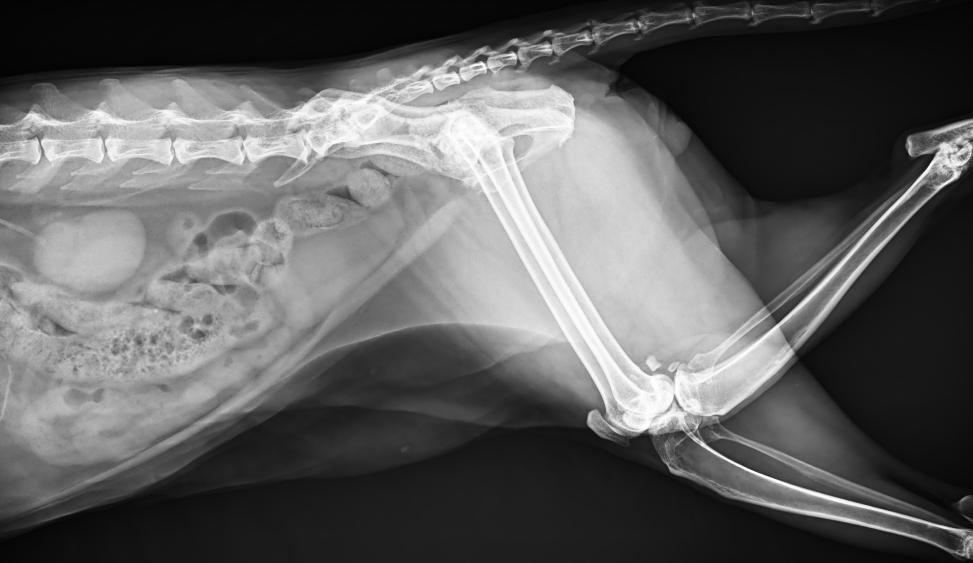

● 17*17大尺寸平板探測器,獲得高質(zhì)量圖像

● 優(yōu)異的空間分辨率及信噪比,提升圖像質(zhì)量

● 采用線噪聲消除技術(shù),使成像質(zhì)量提升40%

● 智能高效的圖像處理軟件,大幅提升圖像質(zhì)量